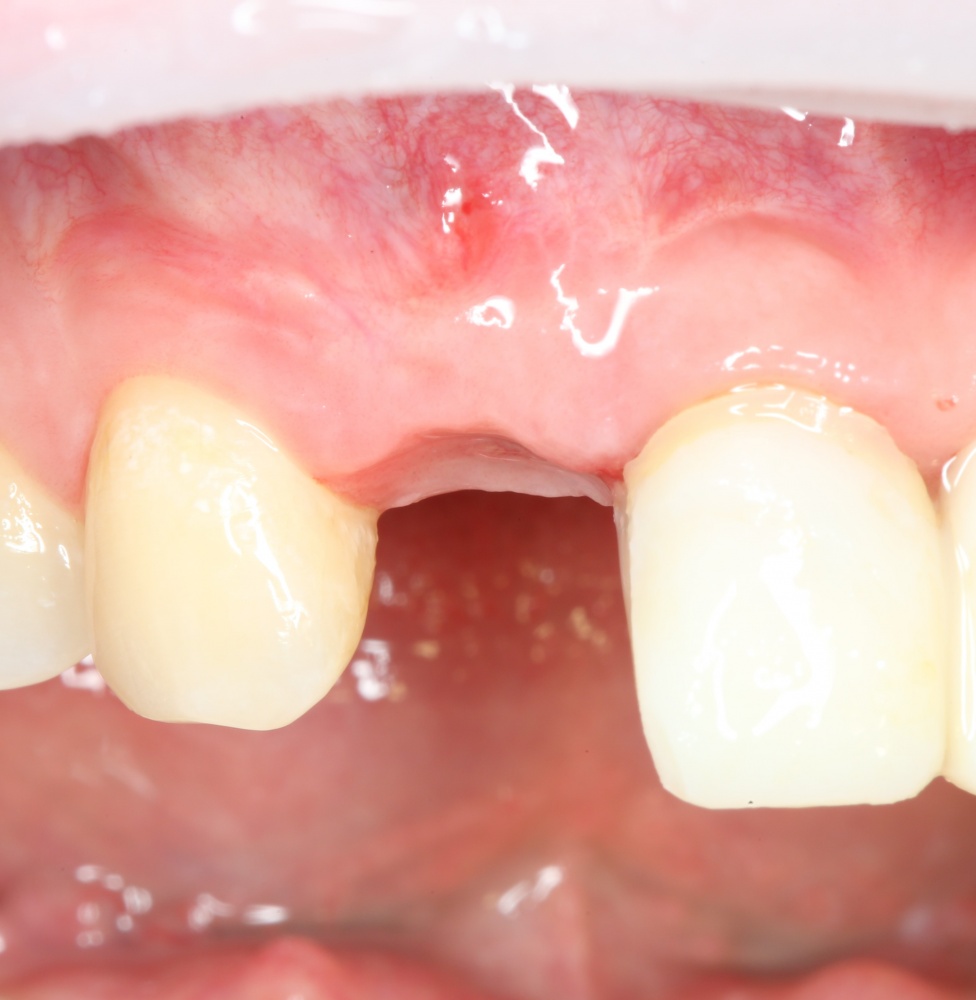

В общем, так и получилось. Уж не помню, почему я наобещал пациентке, что мы поставим ей имплантаты одновременно с остеопластикой. Но я наобещал. И, когда увидел клиническую картину в полости рта:

у меня появились серьезные сомнения, смогу ли я выполнить своё обещание. Вот только не спрашивай меня «Вот чо, сложно было по КЛКТ посмотреть?». Я же не спрашиваю тебя, где ты был в 2013 году, и сделал ли ты домашку. Но, в целом, план операции у нас не поменялся. Как и было оговорено, мы проведем остеопластику с одновременной имплантацией в боковом участке нижней челюсти справа.

Кстати, обрати внимание на ширину альвеолярного гребня (левая картинка). Она чуть меньше 3 мм. Это объясняет, почему я засомневался в возможности установки имплантатов одновременно с остеопластикой. Понятно и без КЛКТ.